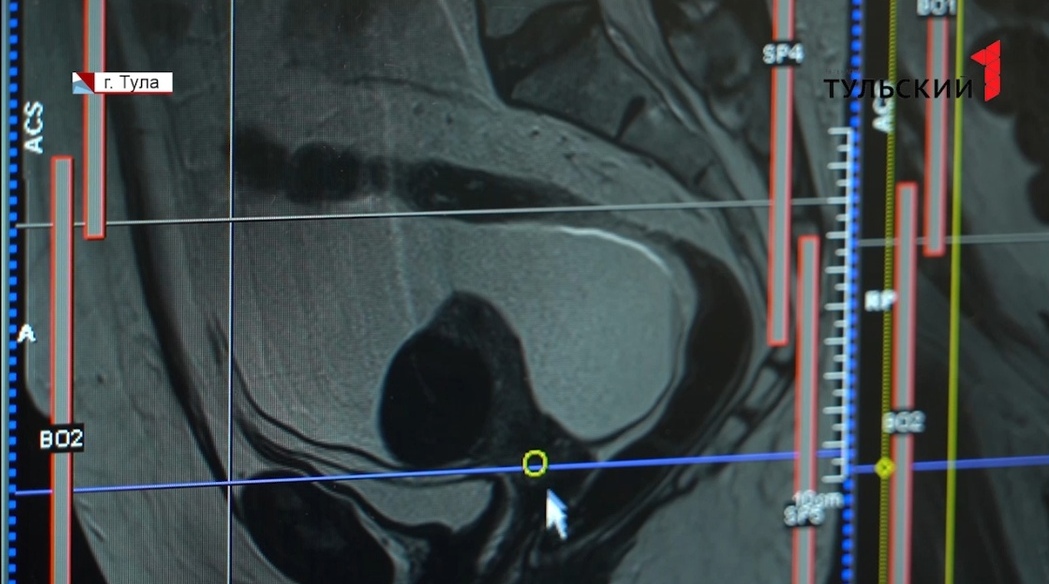

30 минут – столько нужно новому аппарату МРТ, чтобы при помощи электромагнитного поля передать на компьютер изображение внутренних органов пациента. Именно по нему врач определит, раковая опухоль или доброкачественная. Более 250 оттенков серого отображает аппарат, по ним специалисты и считывают нормальные и аномальные ткани. Так разглядеть можно даже самые маленькие опухоли и диагностировать рак на ранней стадии, когда он лучше поддается лечению. Новый МРТ-аппарат для областного онкодиспансера приобрели в рамках нацпроекта «Здравоохранение». Это позволило в два раза сократить ожидание для пациентов, которым такое обследование необходимо.